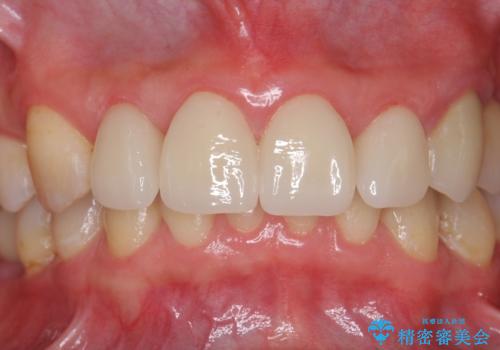

前歯の虫歯 つぎはぎの歯をセラミックに

- 矯正治療後に、前歯の樹脂の詰め物のやりかえを提案していましたが、治療は当時行いませんでした。

その後3年間来院がなく、その間に前歯の虫歯の進行があり、治療を行いました。

やはり、樹脂で虫食い状になってしまうと虫歯が進行しやすくなっているためクラウンがおすすめです。

下の前歯との距離(クリアランス)が大きくは取れなかったため、ジルコニアクラウンではなくe-maxクラウンにしました。

また、歯ぎしりでセラミックがかけるのを防ぐために、就寝時にはナイトガードを装着してもらっています。